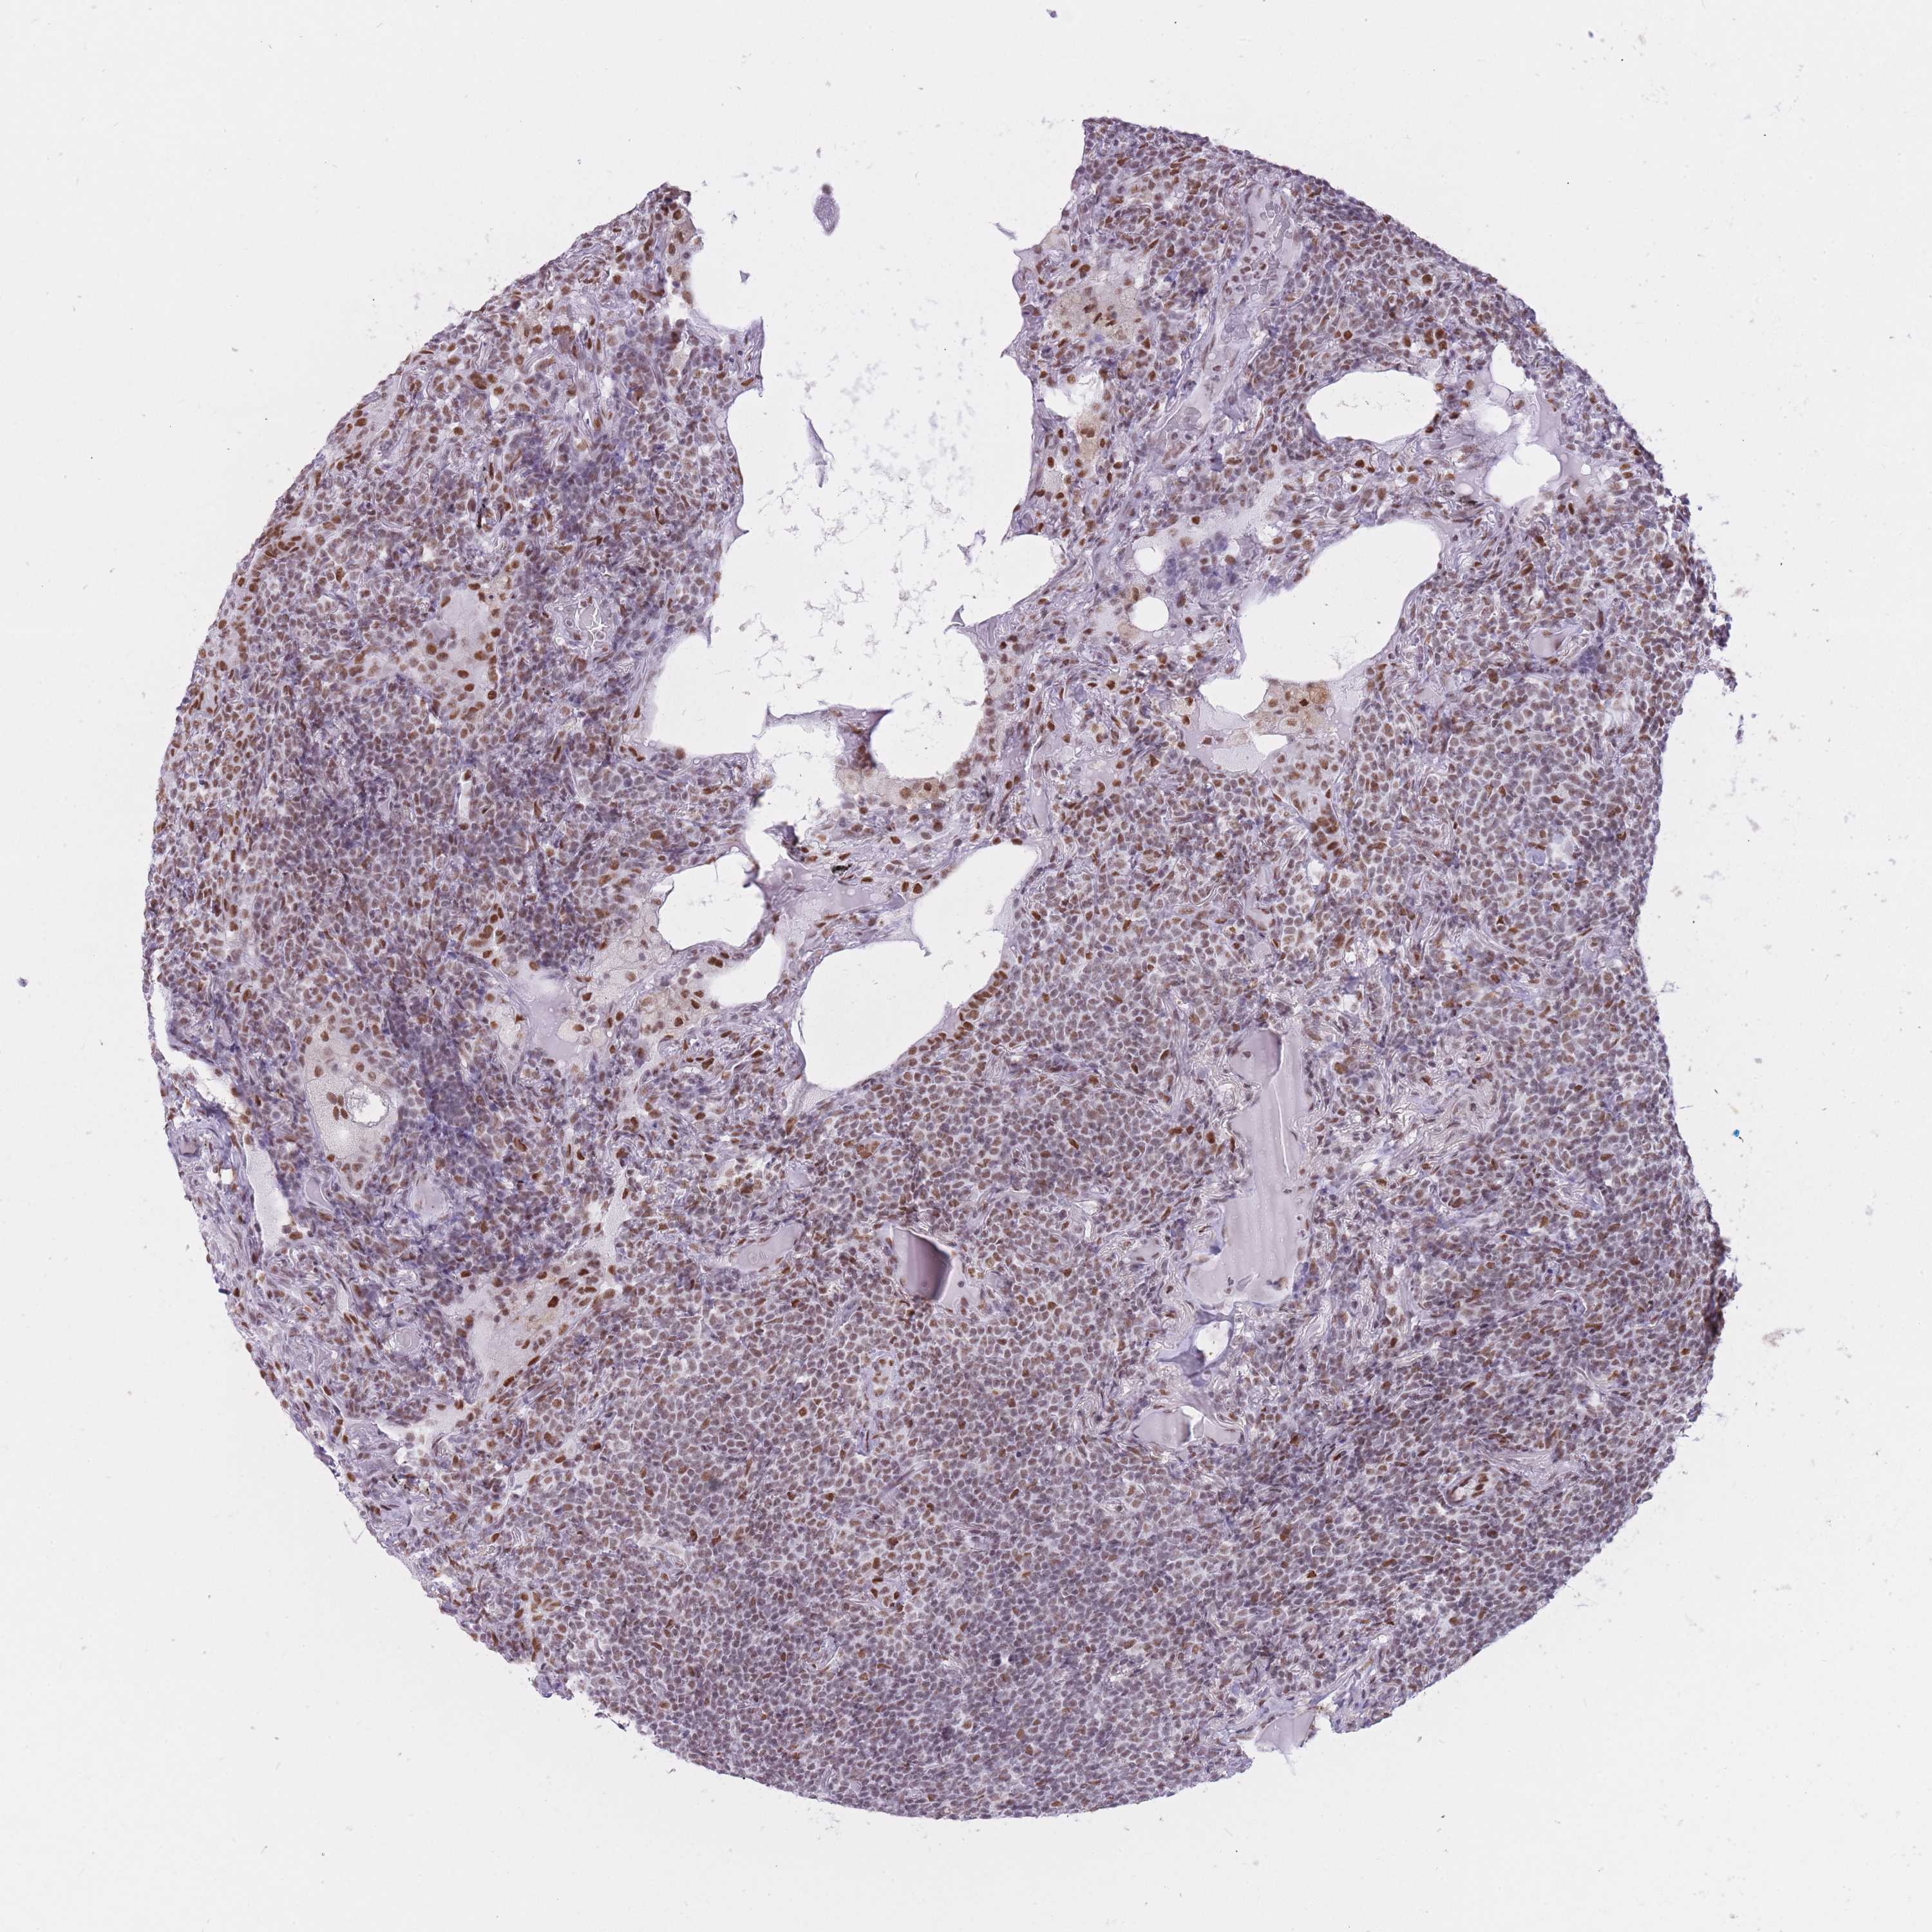

LYMPHOMA - Protein expressioni

A mouse-over function shows sample information and annotation data. Click on an image to view it in a full screen mode. Samples can be filtered based on level of antibody staining by selecting one or several of the following categories: high, medium, low and not detected. The assay and annotation is described here.

Antibody staining in the annotated cell types in the current human tissue is reported as not detected, low, medium, or high, based on conventional immunohistochemistry profiling in selected tissues. This score is based on the combination of the staining intensity and fraction of stained cells.

Each image is clickable and will lead to virtual microscopy that enables deeper exploration of all samples and also displays staining intensity scores, fraction scores and subcellular localization as well as patient and tissue information for each sample.

Antibody HPA046290

Intensity

Strong

Moderate

Weak

Negative

Quantity

>75%

75%-25%

<25%

None

Location

Nuclear

Cytoplasmic/membranous

Cytoplasmic/membranous,nuclear